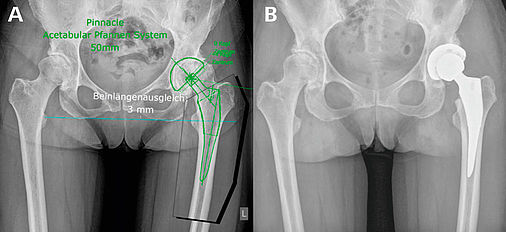

Рентгеновские снимки: Синовит тазобедренного сустава